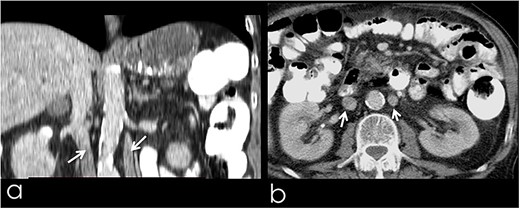

An 82-year-old Caucasian male was diagnosed with obstructive jaundice due to pancreatic duct adenocarcinoma. Computer tomography (CT) and magnetic resonance imaging (Figs 1 and 2) revealed a resectable tumor of the head of the pancreas, a duplicated IVC and a PV trifurcation. The two common iliac veins did not join together at lumbar 4 (L4) vertebra level but ascended separately along the celiac aorta, representing right and left IVC. Specifically, the right external and internal iliac veins joined, forming the right common iliac vein that ran along the abdominal aorta, representing the right IVC. The left IVC formed exactly like the right one while draining to the left renal vein (Fig. 1). This variation can be characterised as ‘type 2a’ in accordance with the classification shown in Fig. 3 (type 2a). Moreover, in our patient, a Whipple procedure was performed without post-operative complications.

(a) CT with contrast demonstrating the trifurcated portal vein (arrow); (b) gross appearance of the duplicated IVC intraoperatively (arrow).